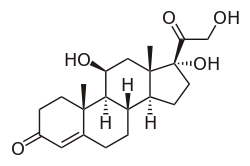

The effects of stress on memory include interference with a person's capacity to encode memory and the ability to retrieve information.[1][2] Stimuli, like stress, improved memory when it was related to learning the subject.[3] During times of stress, the body reacts by secreting stress hormones into the bloodstream. Stress can cause acute and chronic changes in certain brain areas which can cause long-term damage.[4] Over-secretion of stress hormones most frequently impairs long-term delayed recall memory, but can enhance short-term, immediate recall memory. This enhancement is particularly relative in emotional memory. In particular, the hippocampus, prefrontal cortex and the amygdala are affected.[5][6] One class of stress hormone responsible for negatively affecting long-term, delayed recall memory is the glucocorticoids (GCs), the most notable of which is cortisol.[1][6][7] Glucocorticoids facilitate and impair the actions of stress in the brain memory process.[8] Cortisol is a known biomarker for stress.[9] Under normal circumstances, the hippocampus regulates the production of cortisol through negative feedback because it has many receptors that are sensitive to these stress hormones. However, an excess of cortisol can impair the ability of the hippocampus to both encode and recall memories.[2] These stress hormones are also hindering the hippocampus from receiving enough energy by diverting glucose levels to surrounding muscles.[2]

When a receptor within the body senses a stressor, a signal is sent to the anterior hypothalamus. At the reception of the signal, corticotrophin-releasing factor (CRF) acts on the anterior pituitary. The anterior pituitary in turn releases adrenocorticotropic hormone (ACTH).[13][14] ACTH induces the release of corticosteroids and aldosterone from the adrenal gland. These substances are the main factors responsible for the stress response in humans. Cortisol for example stimulates the mobilization of free fatty acids and proteins and the breakdown of amino acids, and increases serum glucose level and blood pressure,[12] among other effects.[15] On the other hand, aldosterone is responsible for water retention associated with stress. As a result of cells retaining sodium and eliminating potassium, water is retained and blood pressure is increased by increasing the blood volume.